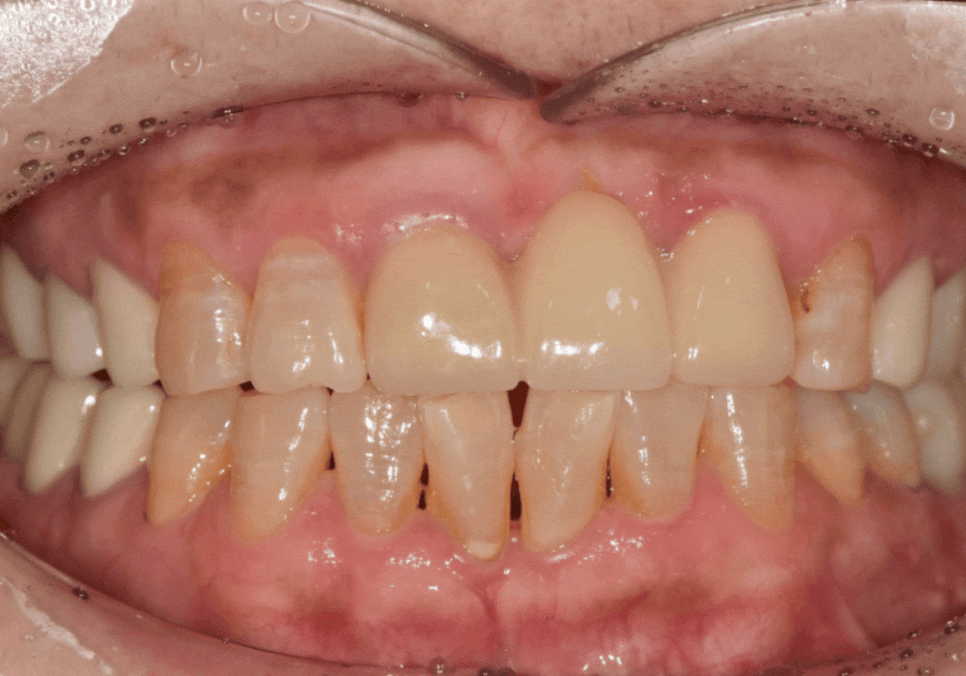

왜 이분은 교정 대신 라미네이트를 선택했을까요?

삐딱하게 뻗은 '나비 모양 앞니', 교정 없이 하루 만에 바뀔 수 있을까?

최근 아래 앞니가 나비 날개처럼 뻗어

고민이셨던 분이 찾아오셨습니다.

물론 교정도 방법이겠지만,

현재의 구강 상태를

종합적으로 고려해 보았을 때,

260102

전체적인 치아 배열은 안정적이라,

앞니를 많이 깎아내지 않고도

충분히 배열을 맞출 수 있는 상태였습니다.

전체 치아를 이동시키는 교정 대신,

틀어진 각도만 정교하게

바로잡는 라미네이트로 가닥을 잡았고,

결과적으로 환자분께

가장 만족스러운 대안이 되었습니다.

살짝 틀어져 있던 앞니가 제 자리를 찾고 나니,

미소가 훨씬 단정하고 편안해 보이시죠?